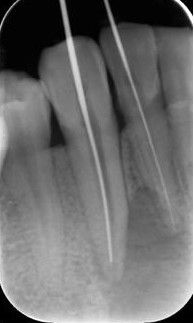

三、确定根管工作长度

应用平行投照X线方法、根管长度测量仪确定根管度,最好插针拍X片